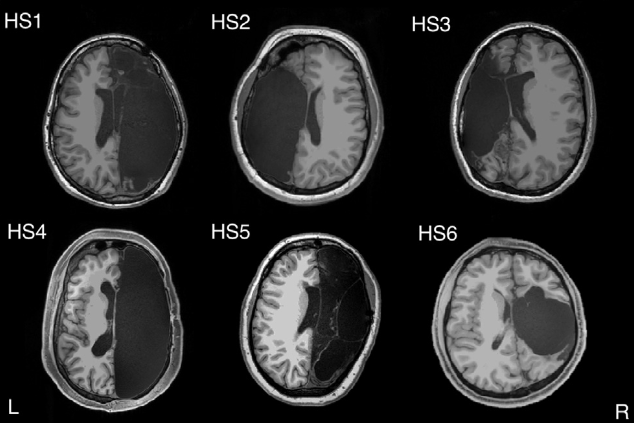

图 1. 半球切除脑解剖

六名成年参与者接受了左侧(n = 2、HS2 和 HS3)或右侧(n = 4、HS1、HS4、HS5 和 HS6)半球切除术。轴向切片在前/后连合线上方最低限度地进行。L, 左; R,右。Cell Reports 29, 2398–2407, November 19, 2019 2399